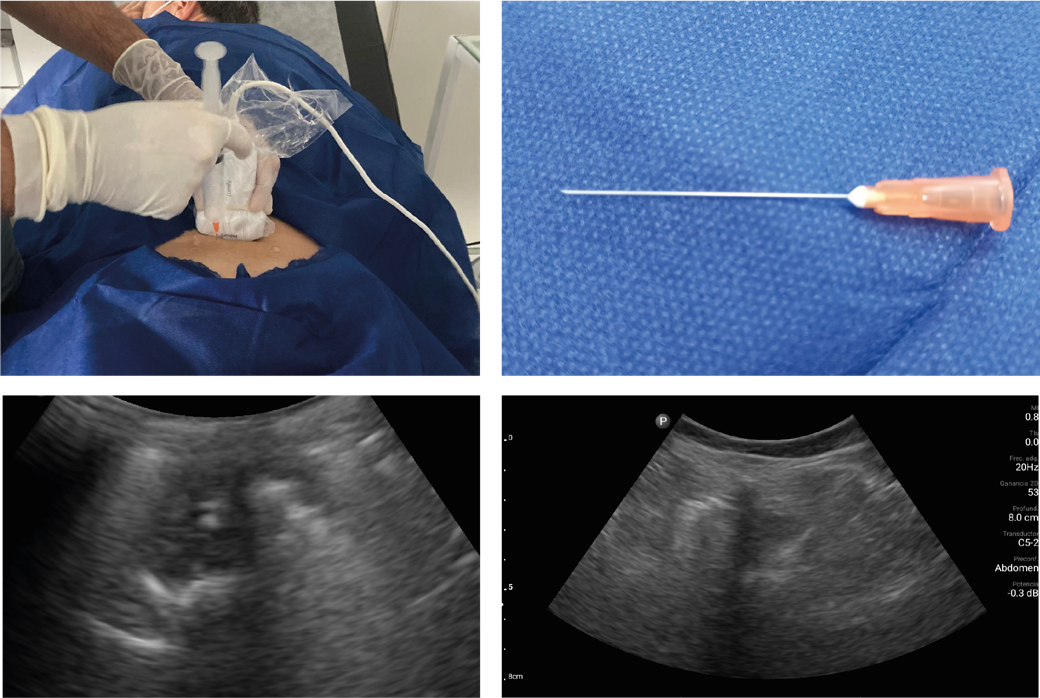

En Ozonoterapia Relevium, las inyecciones paravertebrales de ozono las hacemos en el consultorio, con estrictas medidas de asepsia, guiadas por ecografía, que nos da mayor precisión y seguridad de la difusión del gas en el espesor del músculo. Utilizamos agujas muy finas, 25G de

4 cm de largo, cuando las inyecciones son superficiales o agujas espinales 22 de 8 cm cuando son profundas.

En Ozonoterapia Relevium el Dr. Pablo Castromán realiza estas inyecciones en el consultorio, en estrictas condiciones de asepsia, utilizando la ecografía como guía, ingresando una aguja de 5 cm en el hiato sacro. En éstos casos se realizan 2 o 3 inyecciones en intervalos de 15 días. Después de la punción el paciente permanece en reposo 30 minutos pudiendo seguidamente marcharse a su domicilio.

En Ozonoterapia Relevium, las inyecciones de ozono intra-articular tanto en cadera como en rodilla las hacemos guiados por ecografía.